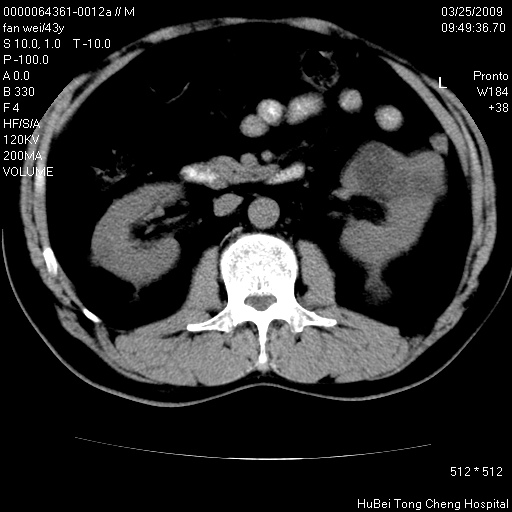

患者 男,43岁。左侧腰部不适两天。平素健康。无家族遗传病史。

腹部彩超提示:1)轻度脂肪肝。2)左肾多发囊性占位性病变;建议行进一步检查。

临床诊断:左肾多发囊性占位性病变,性质待定(多发肾囊肿?)。

双肾ct轴位平扫+增强扫描(层厚10mm,螺距1.0,重建间隔10mm),图像如下:

多囊肾的影像诊断标准:有阳性家族史,年龄<30岁,单侧或双侧肾脏有两个肾囊肿;30~59岁,两侧肾脏各有两个肾囊肿;60岁以上,每侧肾脏有4个囊肿。敏感性和特异性达86%和80%。

此病例影像诊断符合,要结合家族史,腰痛、血尿、尿路感染史,有无高血压等综合判断,如无相应的临床症状,本身病变也无意义了(个人观点)

双肾多发性囊肿

双侧多囊肾!